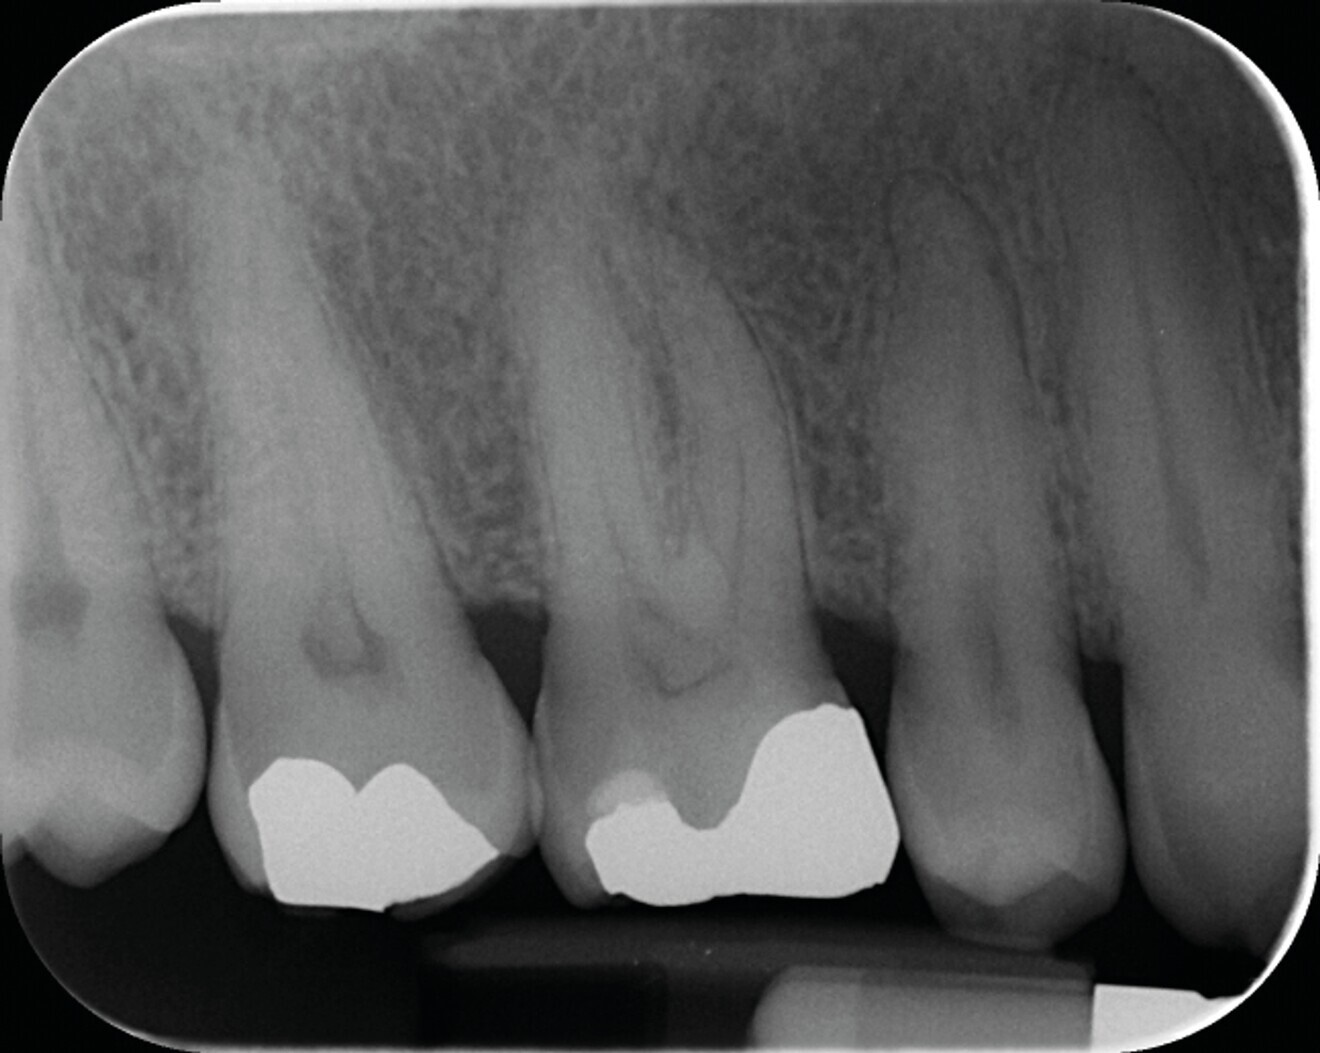

Fig. 7a : Traitement canalaire d’une molaire mandibulaire réalisé avec le système SlimShaper (Zarc – Endoboutik) et obturation avec le CeraSeal (Komet). (a) Radiographie préopératoire.

Fig. 7b : Radiographie postopératoire mettant en évidence la préservation maximale de tissu dentaire dans la partie cervicale de la dent, grâce au système SlimShaper. Cette mise en forme préservatrice n’a pas interféré sur le reste de la procédure, elle permet surtout d’éviter d’affaiblir la dent dans la zone cervicale.